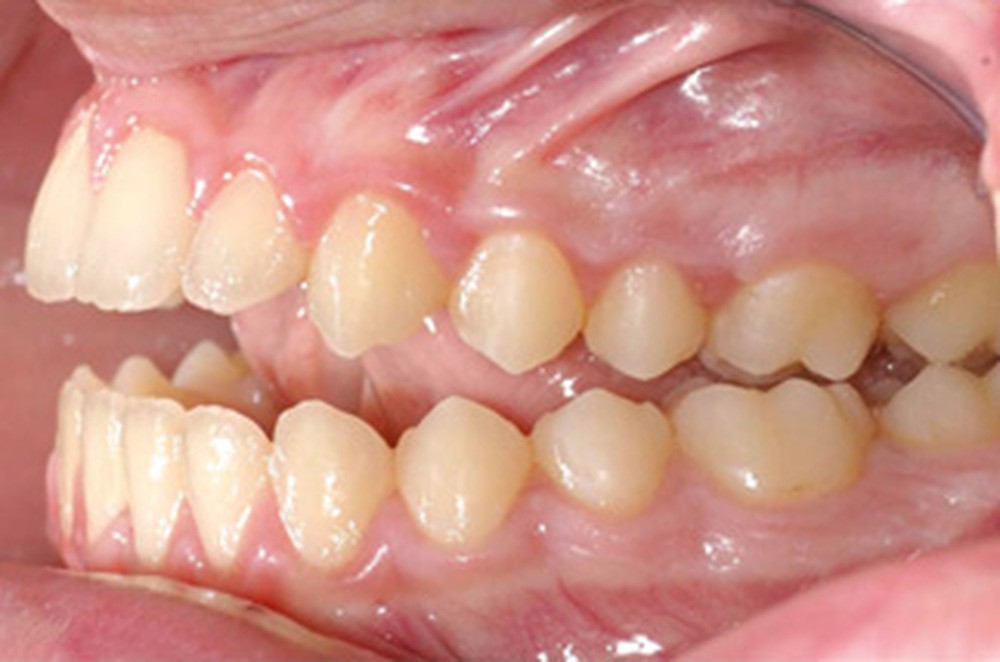

Quelques années plus tard, au moment de démarrer sa prise en charge orthodontique, la patiente présentait à nouveau une béance antérieure, un décalage des milieux incisifs de 2 mm et le problème transversal avait récidivé. Lors de l’examen clinique, elle présentait un inversé d’occlusion bilatéral postérieur et une ventilation buccale exclusive. À la suite du refus de réaliser l’amygdalectomie de façon précoce, elle ronflait toujours et sa déglutition ne s’était pas modifiée malgré des séances d’orthophonie (fig. 7 à 15).